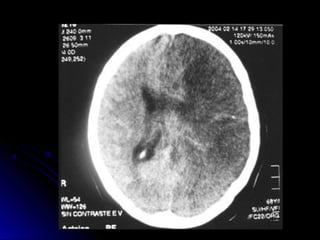

Ubicación de las lesiones en TAC-RNM

DIAGNOSTICO:DIAGNOSTICO: Laboratorio. hemograma, glucemia,ionograma, ESD, tiempo deQuick, KPTT, orinacompleta Evaluación neurológica Radiologíatórax frente ECG y Evaluación Cardiológica, Eco bidi, Doppler TAC cerebral RNM (utilidad técnicadedifusión y percusión) Eco Doppler VasosCuello,  Angio RNM, Arteriografía

Ubicación de laslesiones en TAC-RNM